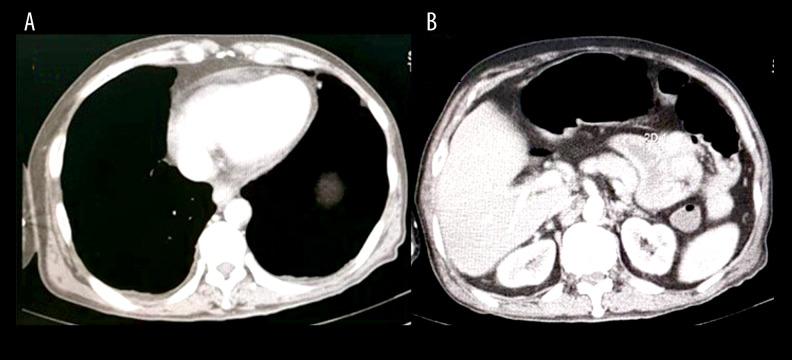

BACKGROUND Triangular QRS-ST-T waveform (TW) electrocardiography pattern has been found to be associated with poor prognosis in patients with ST-segment elevation myocardial infarction (STEMI). It identifies a subset of patients at high risk of both ventricular fibrillation and cardiogenic shock, with high in-hospital mortality. Therefore, aggressive treatment is needed in patients presenting with this electrocardiography pattern. However, this pattern is rarely present in non-ischemic cardiac diseases. CASE REPORT We report the case of a 50-year-old man who came to our emergency room with a chief complaint of gastrointestinal problems and partial bowel obstruction. After failure of initial conservative treatment, laparotomy was planned. Just before the surgery, the patient felt a non-specific chest discomfort and showed ST-segment elevation on ECG and slight elevation of cardiac enzyme. He was then treated for STEMI with an intravenous thrombolytic. However, the degree of ST-segment elevation further increased and showed a TW pattern. Transthoracic echocardiography revealed a moderate pericardial effusion with normal ejection fraction and a normokinetic left ventricle; hence, a diagnosis of acute myopericarditis was made. After treatment with low-dose steroid and colchicine, his symptoms improved, the electrocardiography pattern returned to normal, and the gastrointestinal symptoms resolved. CONCLUSIONS To the best of our knowledge, this is the first case report of an acute myopericarditis presenting with a TW electrocardiography pattern. Myopericarditis should always be considered in the differential diagnosis of acute chest pain and ST segment electrocardiography changes, including TW pattern. The use of echocardiography can help determine the diagnosis of myopericarditis.

我们报告了一位 50 岁男性的病例,他因胃肠道问题和部分肠梗阻的主诉来到我们的急诊室。在初始保守治疗失败后,计划进行剖腹手术。就在手术前,患者感到非特异性胸痛,心电图显示 ST 段抬高和轻度心肌酶升高。随后,他被诊断为 STEMI,并给予静脉溶栓治疗。然而,ST 段抬高程度进一步增加,并出现 TW 模式。经胸超声心动图显示中等量心包积液,射血分数正常,左心室运动正常;因此,诊断为急性心肌炎。给予小剂量激素和秋水仙碱治疗后,他的症状改善,心电图模式恢复正常,胃肠道症状缓解。